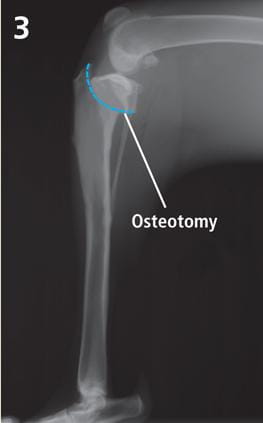

The TPLO involves an osteotomy to reorient the tibial plateau to a near level platform. This provides a biomechanically stable joint. The new tibial plateau angle also reorients the posterior cruciate ligament (PCL), enabling it to function as both the ACL and PCL.

The osteotomy is held in place with a bone plate and screws during healing (approximately three months). The bone plate does not usually require removal.